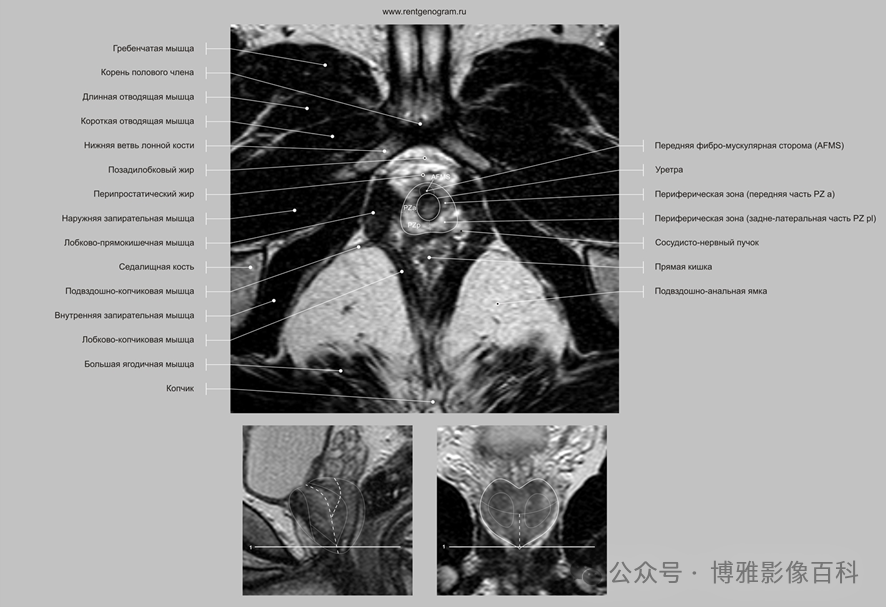

MR 解剖学